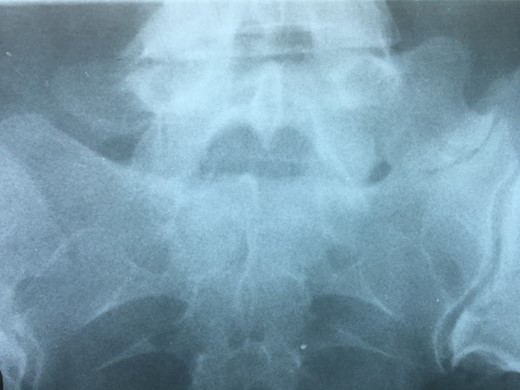

A 42-year-old female presented to the clinic with a history of chronic low back pain. She reported no relevant medical history. She had already been treated in the last 4 years by general practitioners with analgesics and home based physiotherapy with no satisfactory results. She had two previous admissions to the emergency department where morphine was prescribed to control the pain on her lower back. She was under ambulatory treatment with diclofenac, and tizanidine with partial relief of symptoms. Her main complaint was pain on the lower lumbar back with no radiation to the lower extremities. In her physical evaluation she presented limitation to full rotation and bending of the lumbar spine due to pain. Lasegue sign was negative, sensitivity, reflexes, sagittal balance, distal muscular strength and pulses were normal. Radiographs showed an overdeveloped left transverse process of the fifth lumbar vertebra which contacts with the sacrum at the left sacral wing with signs of degeneration at the same site (Fig. 1). Magnetic resonance imaging (MRI) studies were obtained (Figs 2–5). The patient was taken to the operating room where infiltration with 1 mL of lidocaine and 40 mg of Triamcinolone was performed in the pseudoarticulation between the left transverse process and the sacrum under fluoroscopic guidance. She reported a complete relief of pain after the procedure. At three months follow-up she was managed with strengthening and stabilizing exercises for the lumbar spine and postural education was initiated. She remains asymptomatic at her 12 months follow up.

Radiographs showing an overdeveloped left transverse process, which contacts with the sacrum left sacral wing (Castelvi’s Type IIa).